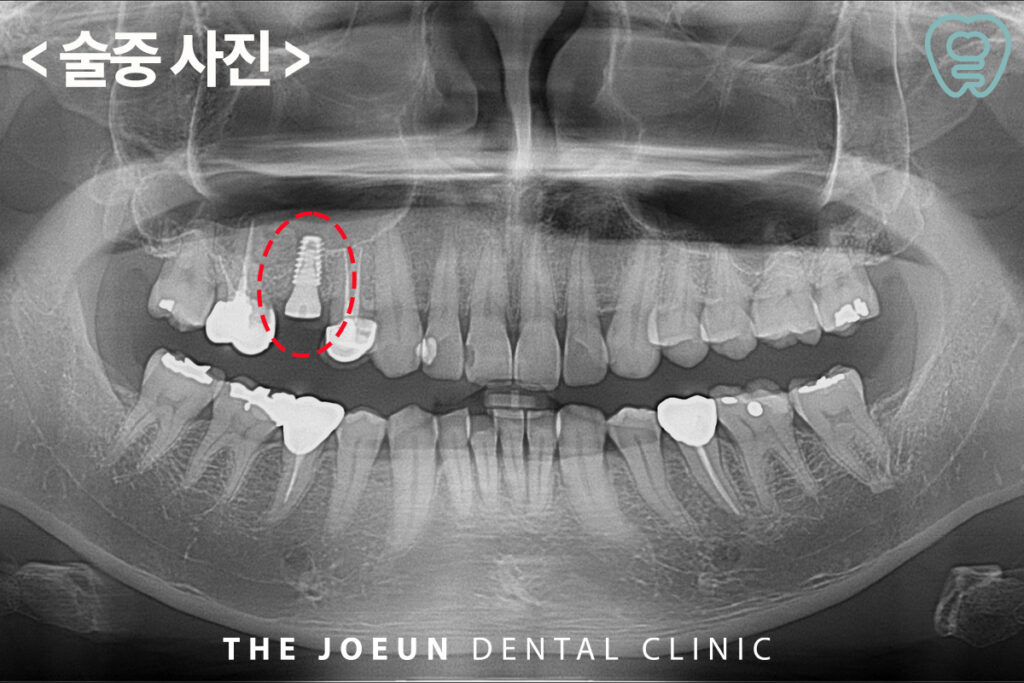

원인이 되는 치아를 발치한 후 뼈이식을 하는 과정에 잇몸을 열어 보았을 때도 많은 양의 뼈가 녹아 있음이 확인되었는데요.

측방 거상법을 통한 뼈이식 후 임플란트 식립을 진행하였습니다.